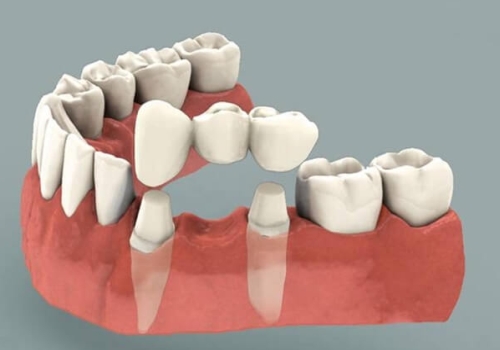

Köprü

Köprü ise bir veya birden fazla diş eksikliğinde, boşluğun önündeki ve arkasındaki dişlerin aşındırılarak-kesilerek küçültülmesi ve bu dişlerden destek alınılarak eksik dişlerin boşluklarının doldurulması amacıyla yapılan protez türüne verilen isimdir.